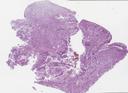

病理切片

SLIDE